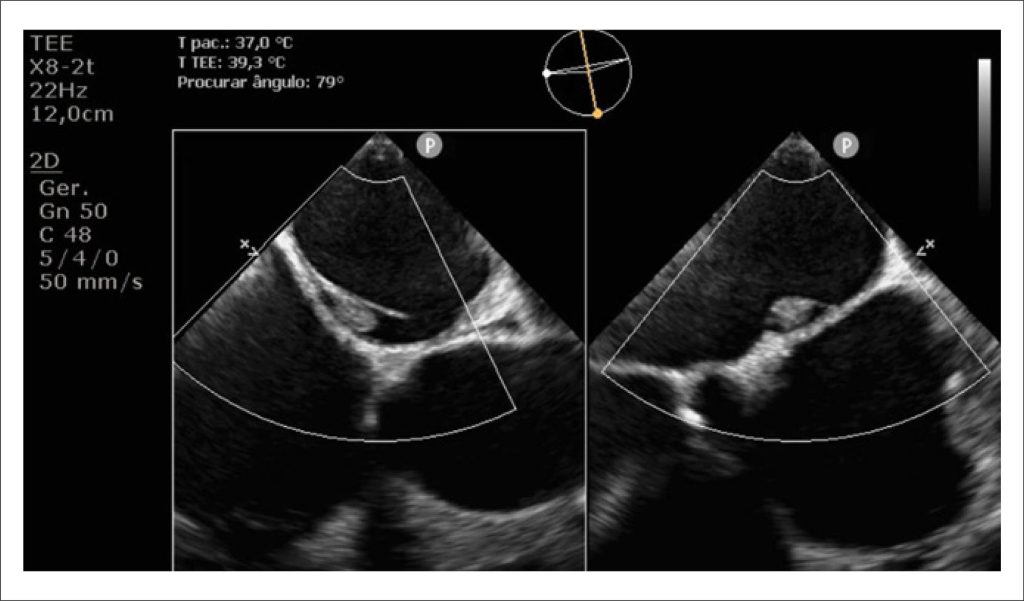

Trombose de Bolsa Septal Atrial Esquerda Detectada Antes de Cardioversão Elétrica: Uma Fonte Rara de Embolismo

A investigação inicial incluiu Eletrocardiograma (ECG) e Ecocardiograma Transtorácico (ETT). O ECG revelou flutter atrial, e o ETT demonstrou dilatação biventricular [diâmetros diastólico/sistólico finais do Ventrículo Esquerdo (VE): 60/51 mm; diâmetro basal do Ventrículo Direito (VD): 54 mm] e disfunção sistólica grave (fração de ejeção do VE: 19%; fração de variação de área do VD: 16%). Identificou-se ainda valva aórtica bicúspide com dupla lesão: estenose aórtica de baixo fluxo e baixo gradiente (velocidade máxima: 3,1 m/s; gradientes máximo/médio: 39/23 mmHg; razão de velocidades: 0,15; área valvar: 0,7 cm; índice de volume sistólico: 17 ml/m) associada a regurgitação aórtica grave (tempo de meia-pressão: 170 ms; fluxo reverso holodiastólico na aorta torácica descendente com velocidade diastólica final de 24 cm/s).

Palavras-chave: Ecocardiografia Transesofagiana; Septo Interatrial; Trombose